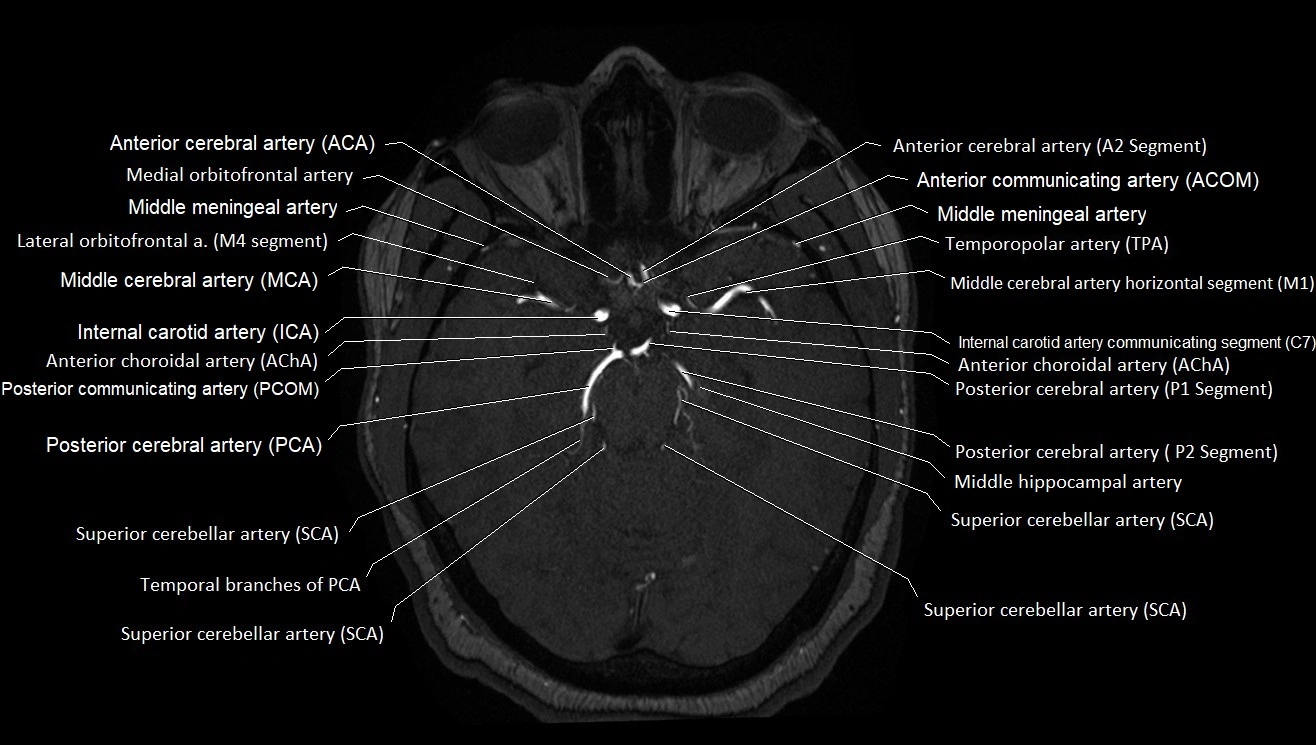

MRA (Magnetic Resonance Angiography):

• Flow-related enhancement makes the AChA appear as a bright, linear vascular signal against suppressed background

• High sensitivity for origin and proximal course; distal branches may be too small to resolve

• Detects stenosis, occlusion, aneurysm, AVM feeders

CT images

image